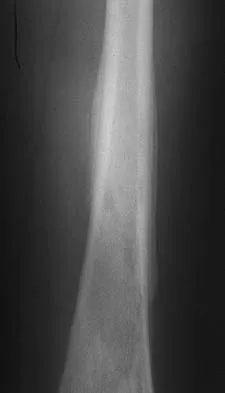

Question 28

A 26-year-old professional rodeo bull rider sustained a grade III midshaft femoral fracture after being thrown from his bull. He underwent closed interlocking intermedullary nailing with a titanium rod, and his recovery was uneventful. Prior to returning to competition, the patient must

Explanation

While it is recommended that a patient gain full range of motion, pain-free function, and symmetric strength prior to returning to vigorous activities, it is absolutely essential that radiographs of the fracture site reveal a circumferential external bridging callus to prevent refracture. This is particularly important for comminuted femoral fractures with various sized fragments. It is also recommended that a return to rodeo riding be postponed for at least 1 year. Brumback RJ, Ellison TS: Intermedullary nailing of femoral stress fractures. J Bone Joint Surg Am 1992;74:106-112. Bucholz RW, Jones A: Fractures of the shaft of the femur. J Bone Joint Surg Am 1991;73:1561-1566.